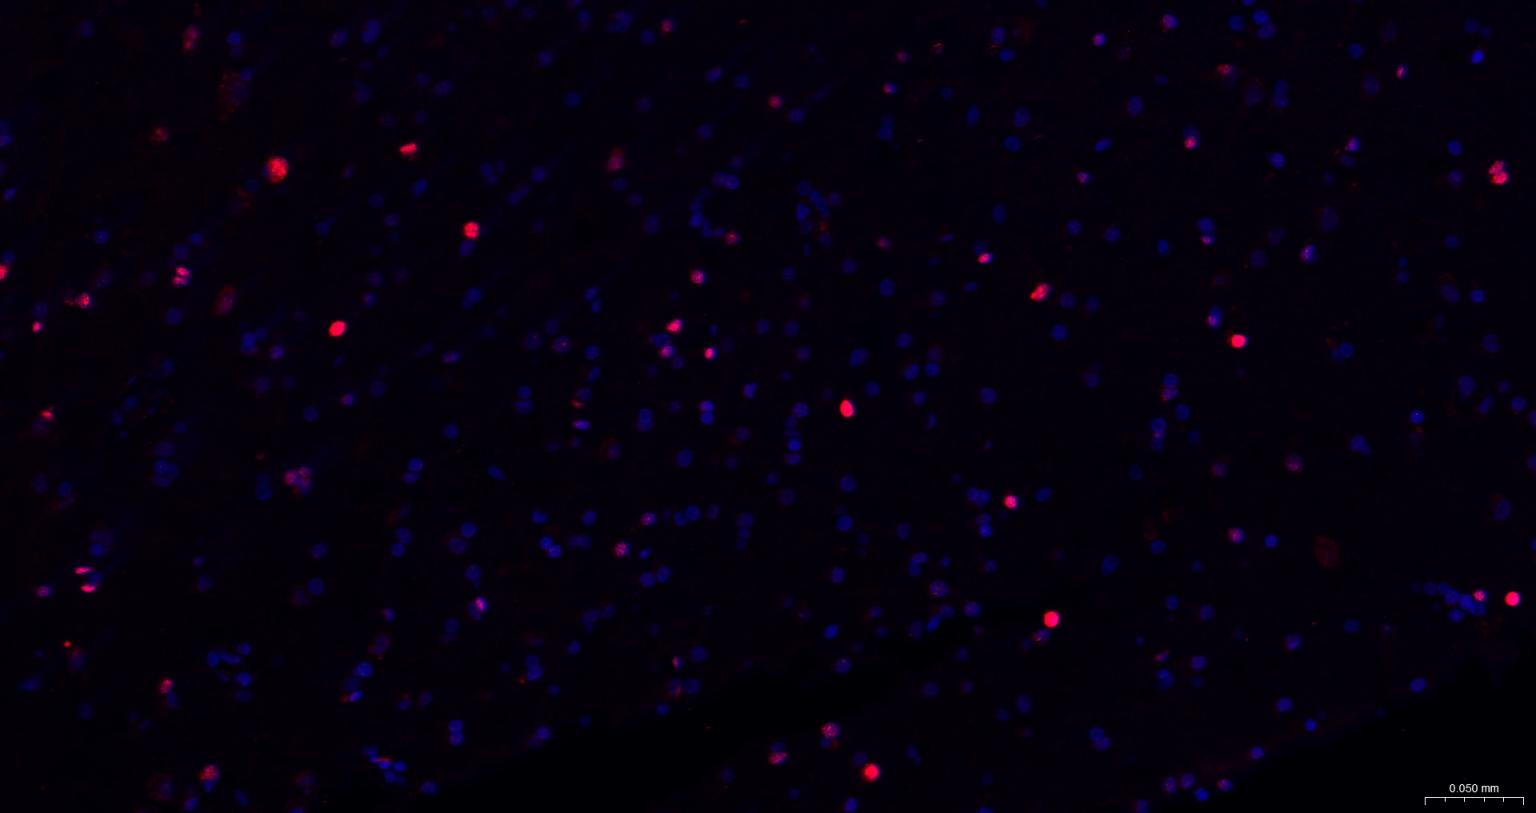

Paraformaldehyde-fixed, paraffin embedded Human Cerebrum; Antigen retrieval by boiling in sodium citrate buffer (pH6.0) for 15 min; The section was incubated with SOX2 Monoclonal Antibody, Unconjugated (bsm-60788R) at 1:200 overnight at 4°C. Followed by conjugated Goat Anti-Rabbit IgG antibody (Red, bs-0295G-BF594), DAPI (blue, C02-04002) was used to stain the cell nuclei.